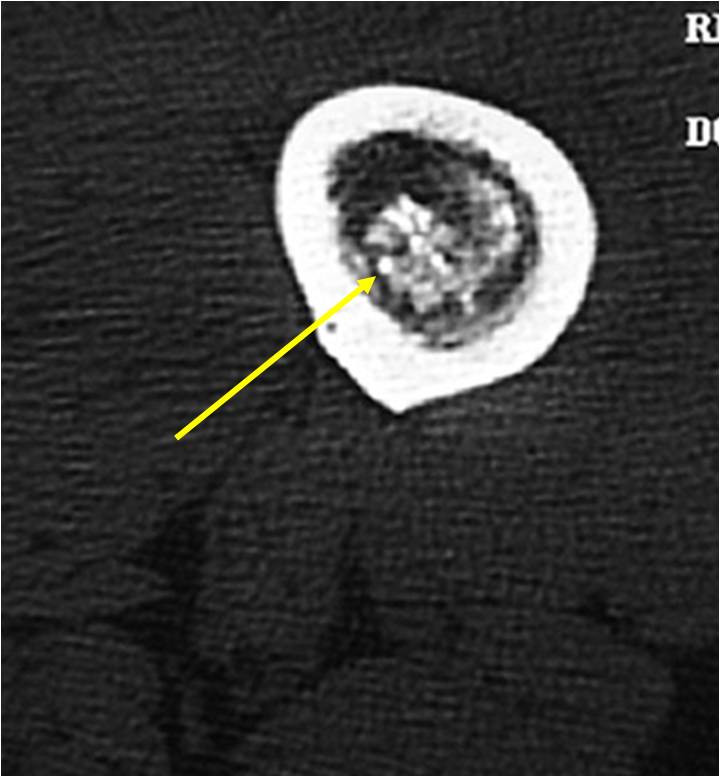

- MRI

- Lobulated margin

- Marked increased intensity long TR images

- Calcified chondroid – low intensity all sequences

MRI:

- Lobulated margin (Lobular Growth Pattern)

- T1 Weighted Images: Intermediate Signal Intensity

- Calcifications will be low signal

- T2 Weighted Images: High Signal Intensity

- High water content shows as high signal on T2 weighted images

- There should never be any cortical destruction nor a soft tissue component. If this exists then the tumor must be a chondrosarcoma.

- Endosteal scalloping and cortical expansion is acceptable for phalangeal tumors. In most benign long bone cartilage tumors there is minimal endosteal scalloping but there should be no cortical expansion nor thickening. There should be no cortical destruction and no soft tissue component associated with an enchondroma. Cortical destruction, periosteal thickening, cortical expansion and a soft tissue component indicates a chondrosarcoma of the long bone.